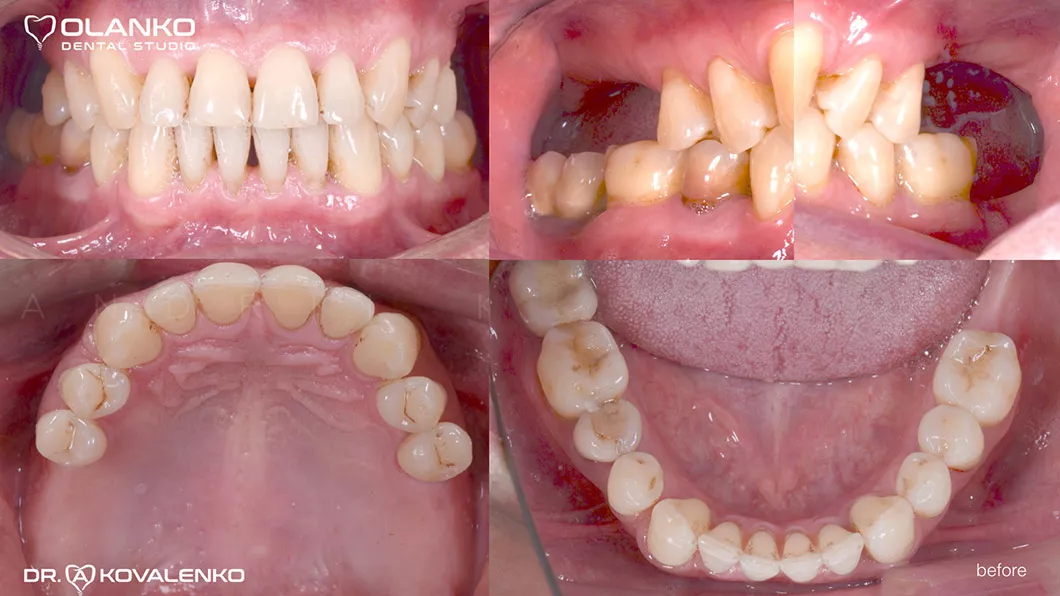

Пациент обратился с жалобами на отсутствие жевательной группы зубов.

Лечение: операция костной пластики на верхней челюсти (двухсторонний синус-лифтинг). Установка 4-х зубных имплантатов на верхней челюсти и один зубной имплантат на нижней челюсти. Пластика мягких тканей в области имплантатов.

Ситуация до

До и После:

до